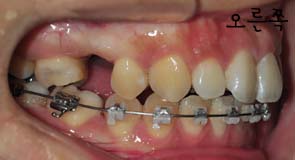

저는 스크류 2개를 입천장에 심어서 이것을 킬본교정장치와 연결아서 당김으로써 앞니가 들어가는것에 효과를 주도록 하였는데요

스크류를 정확히 어느 부위에 심은것이냐고 여쭈니 잇몸뼈라고 하시더라구요

사진과 같이 보시면 입천장에 스크류가 심어졌을때의 모습이 보이시나요? 사진과 같이 두개의 스큐르를 심은후 고무로된 연결고리로 연결하여 킬본교정장치에 걸어서 당기고 당기고~ 를 해주는겁니다 *,*